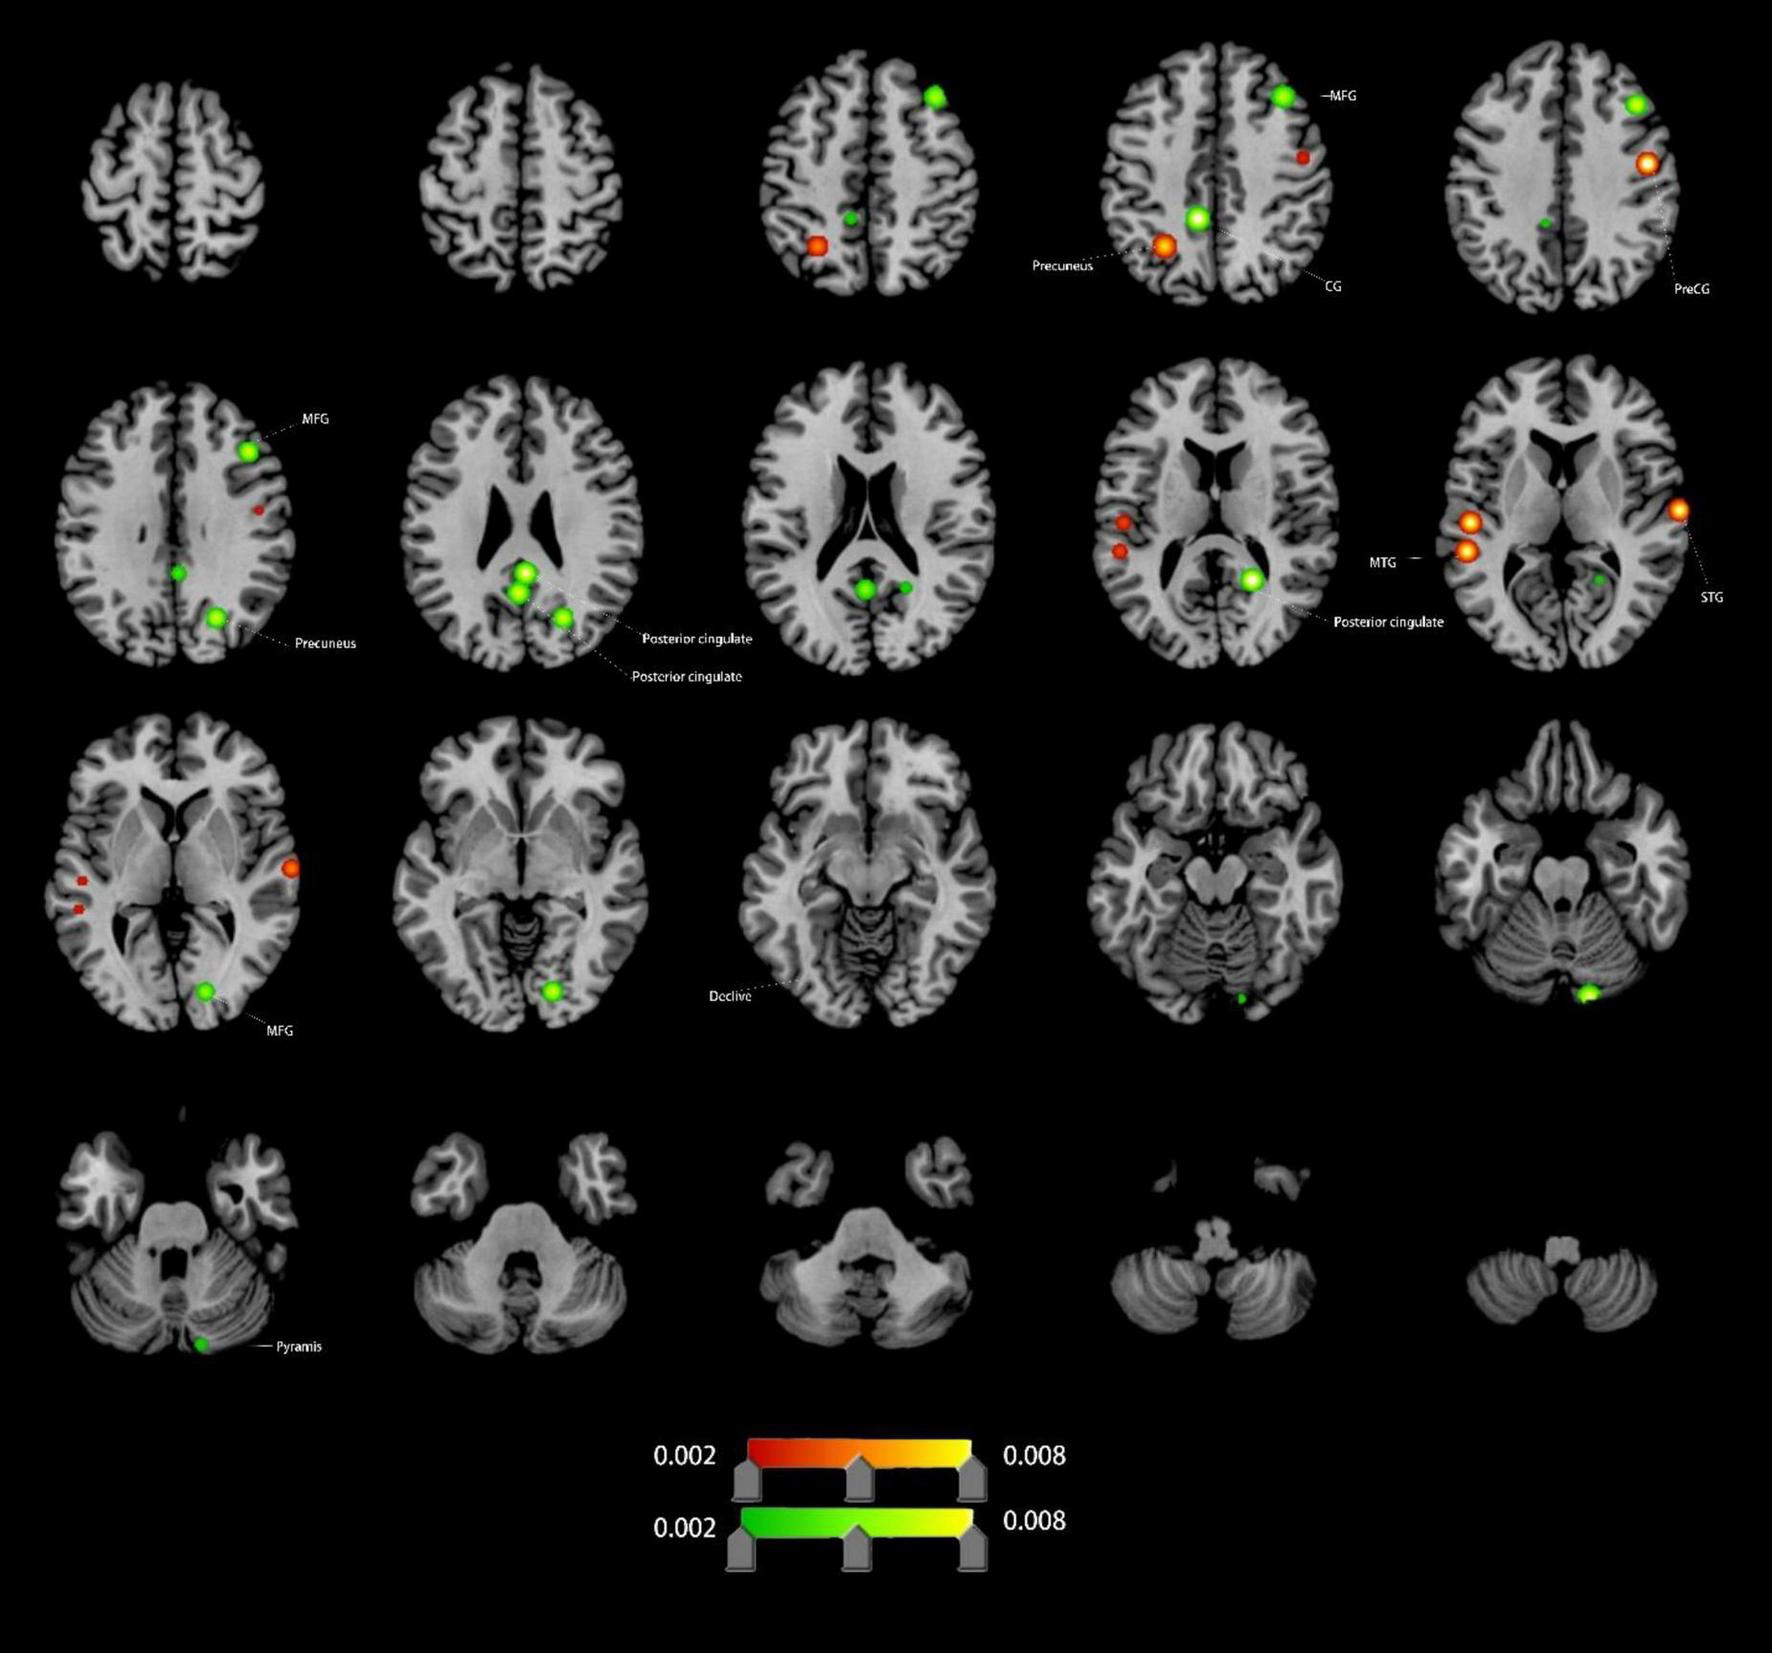

Altered FC in VCI patients

Compared to HCs, VCI patients exhibited significant FC differences. Increased FC (4 clusters): right precentral gyrus (PreCG), left MTG, left precuneus, right superior temporal gyrus (STG); Decreased FC (9 clusters): left cingulate gyrus (CG), both posterior cingulate, right precuneus, right lingual gyrus (LING), right pyramis, right PreCG, and right MFG (Figure 4 and Table 1).

FIGURE 4

Brain regions showing increased/decreassed FC in VCI patients compared to HCs. Red indicates regions of increased FC values. Green indicates regions of decreased FC values. PreCG, precentral gyrus; MFG, middle frontal gyrus; MTG, middle temporal gyrus; STG, superior temporal gyrus; CG, cingulate gyrus; LING, lingual gyrus.

FC Changes: Enhanced FC in the right STG, MTG, and left precuneus may reflect enhancements in speech perception, auditory word comprehension, and language processing, as complex cognitive processes that require neural integration across multiple brain regions (Bhaya-Grossman and Chang, 2022; Dadario and Sughrue, 2023; Liu et al., 2023; Sugimoto et al., 2023). Conversely, reduced FC in the cingulate gyrus (CG), posterior cingulate, and precuneus reflects DMN disintegration, correlating with impaired self-referential processing and memory consolidation (Bubb et al., 2018; Dadario and Sughrue, 2023; Foster et al., 2023; Leech and Sharp, 2014).